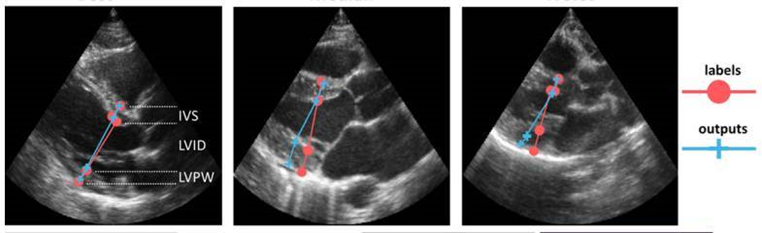

Gjennom det NFR-støttede prosjektet INCUS (2016-2019) har NR sammen med Vingmed utviklet metoder for automatisk gjenkjenning av synsvinkel inn mot hjertet, for automatisk valg av ønsket type Doppler-målinger og for automatiske målinger av avstander i ultralydbildene. Flere av løsningene er integrert i skanneren. Dette samarbeidet om utvikling av nye metoder for mer intelligente ultralydsskannere fortsetter nå gjennom IPN-prosjektet EchoAI (2020-2023) og gjennom Visual Intelligence (2020-2028), senter for forskningsdrevet innovasjon innen AI for komplekse bildedata.

Gilbert, A., Holden, M., Eikvil, L., Aase, S. A., Samset, E., & McLeod, K. (2019). Automated left ventricle dimension measurement in 2D cardiac ultrasound via an anatomically meaningful CNN approach. I Q. Wang, A. Gomez, J Hutter, K. McLeod, V. Zimmer, O. Zettinig, R. Licandro, E. Robinson, D. Christiaens, E. Abaci Turk & A. Melbourne (Eds.), Smart Ultrasound Imaging and Perinatal, Preterm and Paediatric Image Analysis (1st ed., pp. 29-37). Springer. DOI: 10.1007/978-3-030-32875-7.